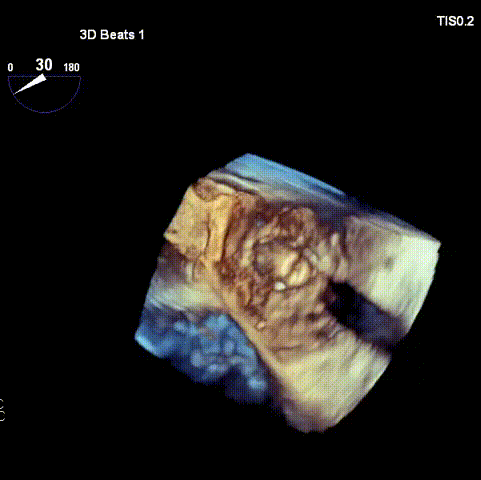

术后3D重建:

三尖瓣“瓣中瓣”支架形态位置良好